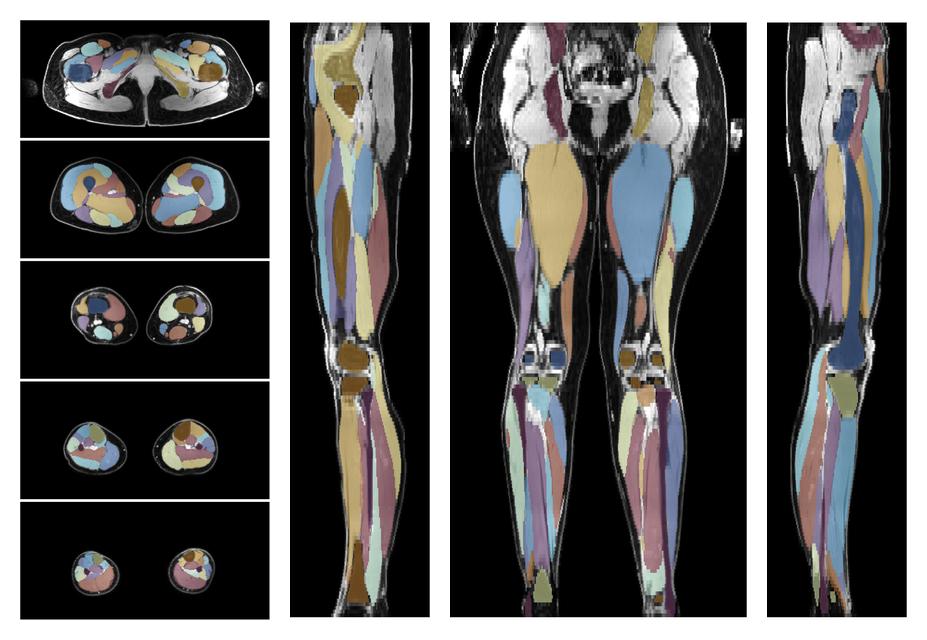

• Automated muscle and bone segmentation.

Overlay of automated muscle segmentation labels on dixon water image.